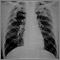

Cáncer metastásico al pulmón

Los tumores metastásicos en los pulmones son cánceres que se desarrollan en otros lugares del cuerpo (u otras partes de los pulmones) y se propagan a través del torrente sanguíneo o el sistema linfático a los pulmones. Es diferente al cáncer pulmonar que comienza en los pulmones.

El médico o el personal de enfermería lo examinarán y le harán preguntas sobre su historia clínica y los síntomas. Los exámenes que pueden realizarse son: